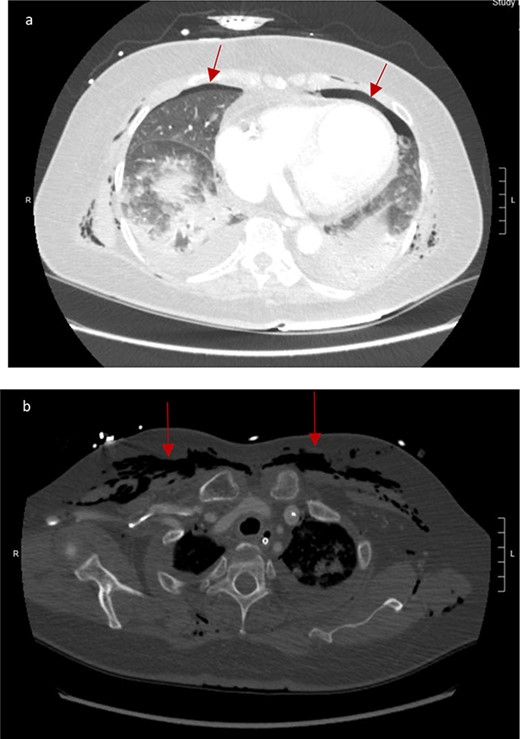

CT scan showed small bilateral pneumothoraces (Fig. 1a) in the setting of several mildly displaced anterior rib fractures with associated subcutaneous emphysema (Fig. 1b), as well as extensive intraperitoneal (Fig. 2), extraperitoneal and retroperitoneal (Fig. 3) air. However, imaging was negative for evidence of perforation. Given concern for abdominal compartment syndrome as evidenced by abdominal distension on exam, initially elevated peak pressures to 24 immediately following intubation, and CT findings of pneumoperitonum, the General Surgery service was consulted for evaluation and further assistance with management. On clinical exam, the patient’s abdomen was distended without tenderness, guarding, or rebound. Laboratory results were notable for white blood cell count of 21.1 per mm3, platelet count of 314 per mm3, and a whole blood lactate of 8.1 mmol/l. Her leukocytosis, though only mildly increased from her baseline of 15 over the previous days, was attributed to known Staphylococcus bacteremia for which she was on antibiotic therapy with a contribution from her shock and PEA arrest. Given the patient was hemodynamically stable with no signs of an acute abdomen, we decided to manage with serial abdominal exams without operative intervention. The patient was closely followed over the subsequent 5 days, during which time she remained stable; she no longer required pressors and was weaned to trach collar on post-arrest Day 2; her white blood cell count continued to downtrend and normalized post-arrest Day 7 as she remained on antibiotic therapy; no additional abdominal imaging was obtained, given her very benign abdominal exam. Operative management was never utilized and she remained asymptomatic. While in the intensive care unit, the patient improved and she was able to engage in physical and occupational therapy despite the pneumothoraces. She was discharged to a long-term acute care hospital on hospital Day 36.

Bilateral retroperitoneal air surrounding right and left kidneys.